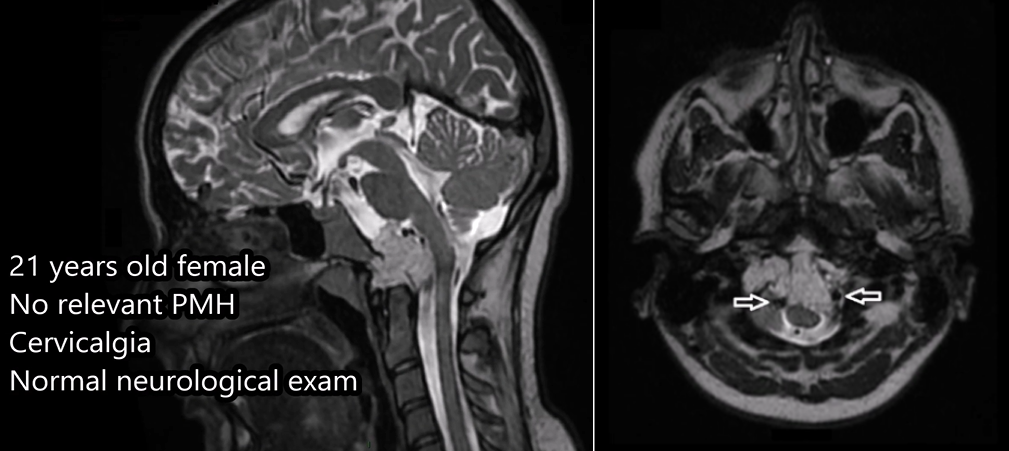

21岁女性颅颈交界处脊索瘤,前外侧入路成功切除肿瘤

21岁法国女孩因颈部疼痛就诊,MRI发现枕骨大孔、颅颈交界区肿瘤伴椎动脉受累、骨质破坏及硬膜内侵犯。福教授采用显微镜+内镜双镜联合精准切除肿瘤,术后辅以枕颈融合术确保脊柱稳定性,成功化解这一高危手术难题。

术前MRI